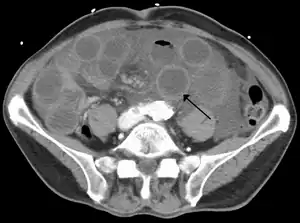

![]() | |

| Computed tomography (CT) showing dilated loops of small bowel with thickened walls (black arrow), findings characteristic of ischemic bowel due to thrombosis of the superior mesenteric vein. | |

Computed tomography

Computed tomography (CT scan) is often used.[29][30] The accuracy of the CT scan depends on whether a small bowel obstruction (SBO) is present.[31]

Early findings on CT scan include:

- Intestinal mesenteric edema[29]

- Bowel dilatation[29]

- Bowel wall thickening[29]

- Intestinal mesenteric stranding[32]